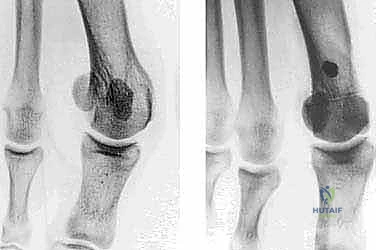

* بروز المفصل: هذا الانحراف المتعاكس يؤدي إلى بروز رأس العظمة المشطية الأولى، مكوناً الكتلة العظمية المؤلمة التي نراها من الخارج.

* الزاوية المفصلية المشطية البعيدة (DMAA): في الحالات المتقدمة، يتشوه سطح المفصل نفسه ويميل بزاوية غير طبيعية. الجراحات التقليدية تفشل في علاج هذه الزاوية، وهنا تبرز أهمية تقنية شفرون ثنائية المستوى التي يطبقها الدكتور هطيف لتصحيح هذه الزاوية بدقة متناهية.

- التصوير بالأشعة السينية الدقيقة (Weight-Bearing X-Rays): وهي خطوة حاسمة. يجب أن تؤخذ الأشعة والمريض واقف (يحمل وزنه على قدمه) لإظهار الحجم الحقيقي للتشوه.

- القياسات الهندسية لزوايا القدم: يقوم الدكتور هطيف بقياس زوايا محددة لتحديد نوع الجراحة، أهمها: